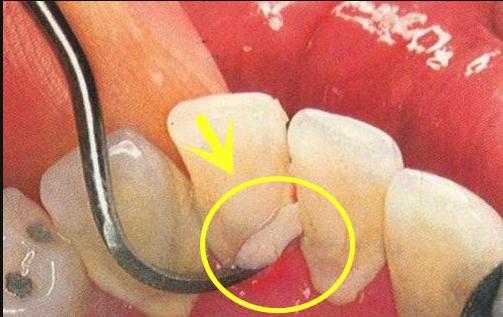

每个人牙齿后面及缝隙处,或多或少都会积攒东西,这是陈年老酿。是多年来,不好好刷牙齿背面,不清理牙缝,所形成的。牙齿后面扣下来一块闻起来很臭,这就是牙结石!

牙结石会和食物残渣,堆积在牙齿表面,初期是软垢,时间一长就硬化了。扣一块下来,使劲捏一捏,是一种沙沙脆的感觉,跟风化的沙石一样。牙结石一旦形成,会不断刺激牙龈,压迫牙龈,促使牙龈萎缩,牙龈出血。时间长了牙槽骨就会萎缩,牙根逐渐就漏出来,牙齿开始敏感,发酸发疼。